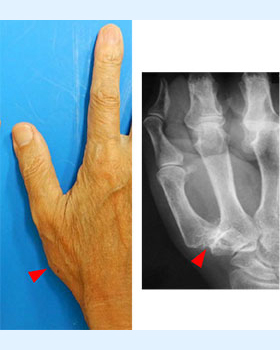

親指の付け根の関節である母指CM関節で痛みや腫れが出る病気です。